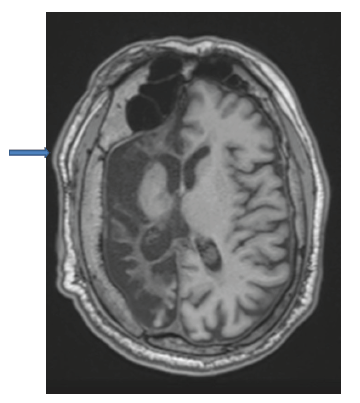

En los estudios complementarios, el paciente cuenta con electroencefalograma que evidencia actividad epileptiforme focal a derecha y episodios motores paroxísticos no epilépticos, y resonancia magnética de cráneo con protocolo de epilepsia (secuencias T2 coronal, FLAIR axial y T1 axial) que muestra una extensa disminución volumétrica en todo el hemisferio cerebral derecho, que se asocia a gliosis cortical y subcortical. Además, también se observó un engrosamiento compensatorio de la calota craneana y un aumento del tamaño del hemiseno frontal (figuras 1, 2 y 3).

T1 axial

Figura 3: T1 axial

Fuente: los autores con base en la historia clínica.